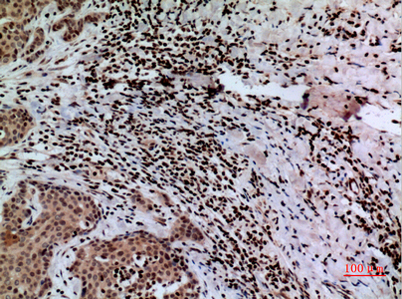

Product name: CacyBP rabbit pAb

Dilutions: Western Blot: 1/500 - 1/2000. IHC-p: 1/100-1/300. ELISA: 1/20000. Not yet tested in other applications.

Immunogen: The antiserum was produced against synthesized peptide derived from the C-terminal region of human CACYBP. AA range:171-220